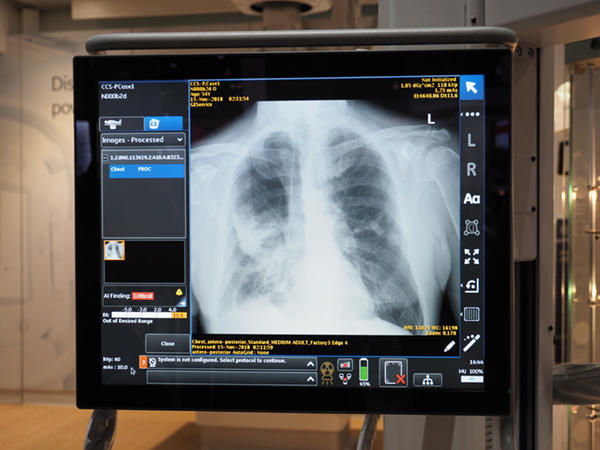

GE Healthcare(GEヘルスケア)のX線撮影装置関連では,移動型X線撮影装置「Optima XR240amx」に搭載されるAIプラットフォーム“Edison”の診療支援システム“Critical Care Suite”(FAD未承認)が,FDA承認待ちの段階になっていることがアナウンスされた。ブース全体では,Edisonの技術が50近く紹介されているが,その中でも診断・検査支援システムとして,最も臨床現場の近くにやって来た技術と言えるのがCritical Care Suiteである。前回のRSNAでは参考出展であったが,製品化に向けて確実に開発を進めてきた。

一般的に,移動型X線撮影装置の検査では,担当技師は短時間で多くの撮影を行わなければならない。特に,救急での検査オーダも多く,被検者の状態も重篤な場合もあり,正確な撮影と速やかな読影が重要なカギを握る。そこで,Critical Care Suiteでは,撮影直後に気胸の有無を判定して,気胸の確信度などの判定結果を示すことで,速やかな治療への移行を支援する。気胸の判定のほかにも,ポジショニングに問題があった場合はアラートを出すため,診療放射線技師の教育にも役立てることができる。

気胸を検出して診療を支援する“Critical Care Suite”(FDA未承認)

Critical Care Suite搭載の「Optima XR240amx」